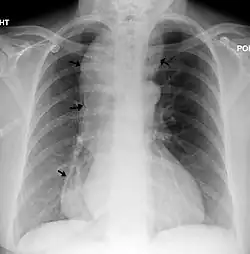

| Chest x-ray of an individual with achalasia. The arrows point to the areas of extreme esophageal dilation. | |

A positive barium swallow will display the narrowing of the distal oesophagus in a 'bird beak' or 'champagne class' fashion, aperistalsis, minimal LES opening and oesophageal dilation as the main indicator of the disease.[4][5] Minimal barium will be present in the stomach.[5] However, these diagnostic findings are not always present in the early onset of the disease and so a normal oesophagogram is not an indication of a lack of disease.[5]